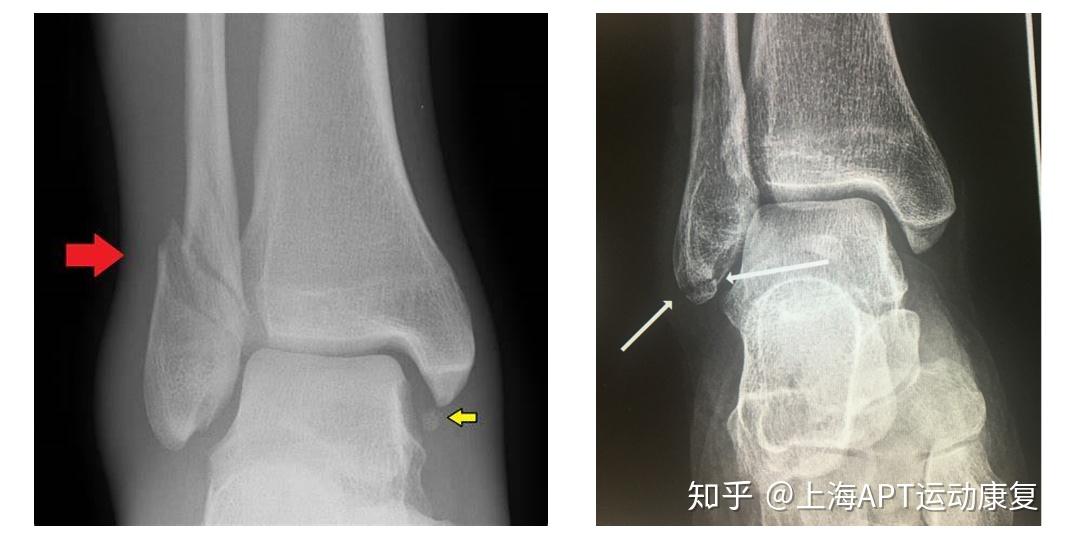

外踝扭伤——撕脱骨折的手术知识清单

图片尺寸500x733